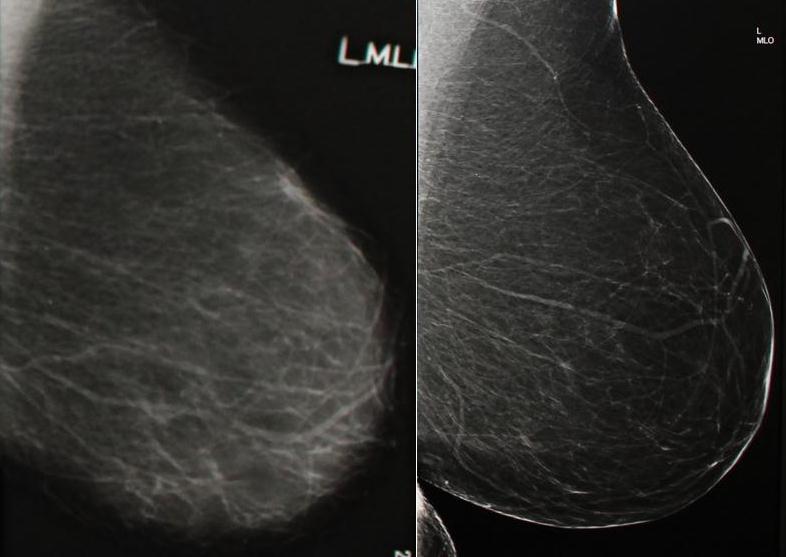

VERNON – North Okanagan residents are benefiting from recent enhancements to Vernon Jubilee Hospital’s imaging department, including a new digital mammography machine.

The new digital mammography unit replaces an older analog system, which performed nearly 7,000 screenings and 3,500 diagnostic examinations on patients last year.

The new unit enhances the ability to detect micro-lesions thanks to higher quality resolution. It also reduces the amount of radiation patients are exposed to by approximately 30 per cent.